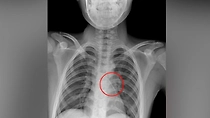

Московские хирурги спасли 11-летнего мальчика, вдохнувшего булавку